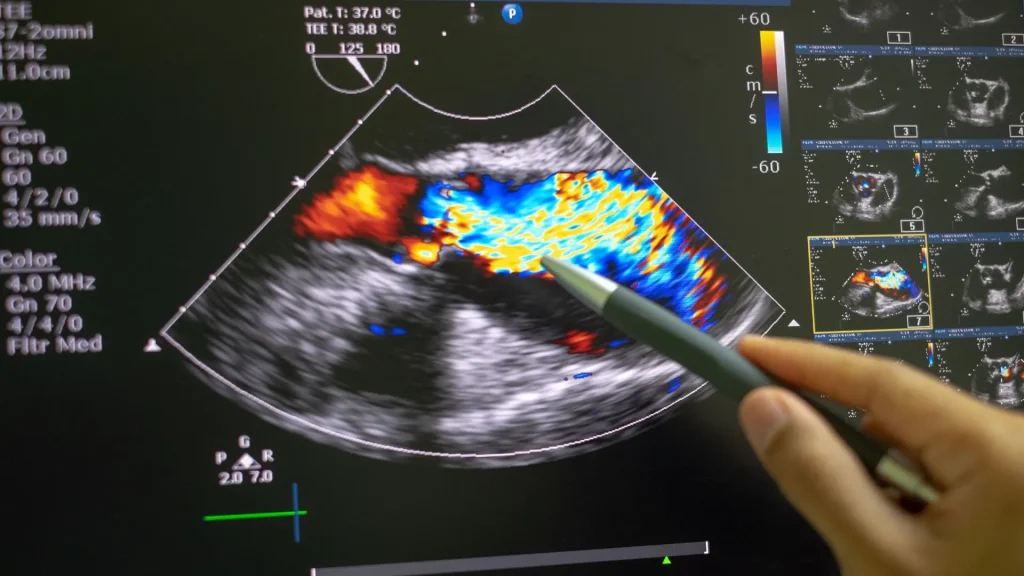

Kualitas Gambar yang Lebih Baik

Layar modern pada tablet dan smartphone sudah mendukung resolusi tinggi. Hal ini memberikan tampilan gambar USG yang lebih jelas, membantu diagnosis menjadi lebih akurat.